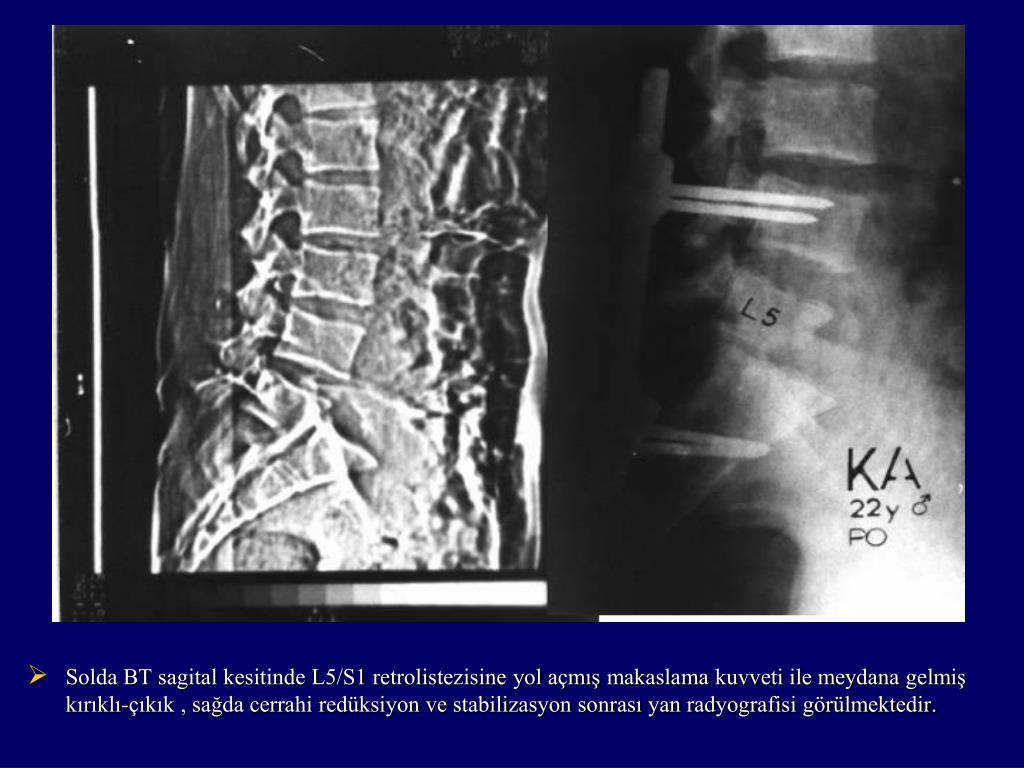

7. Solda BT sagital kesitinde L5/S1 retrolistezisine yol açmış makaslama kuvveti ile meydana gelmiş kırıklı-çıkık , sağda cerrahi redüksiyon ve stabilizasyon sonrası yan radyografisi görülmektedir.